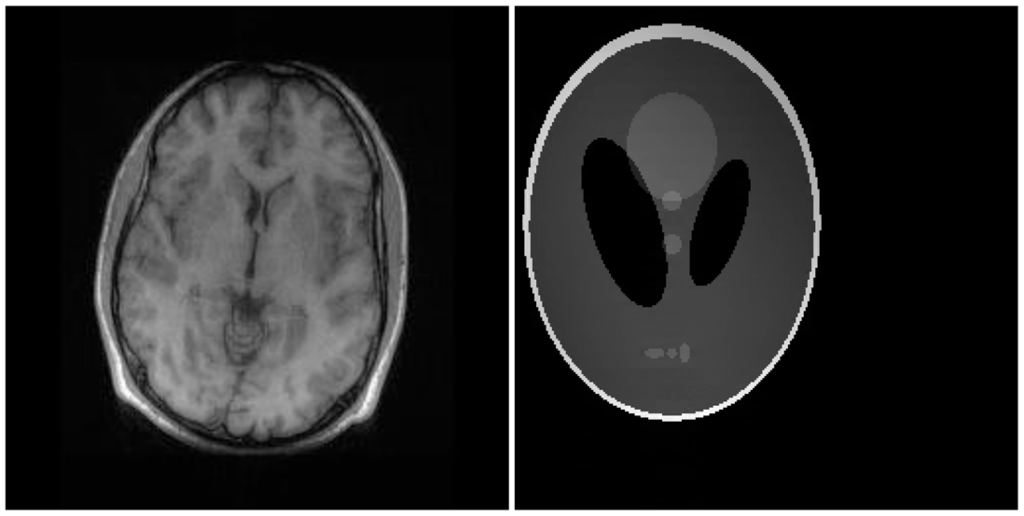

There are two sets of ground-truth data used for our experimental evaluation (Figure 7). The brain data and the Shepp-Logan phantom have been used previously in [4]. The brain data is a fully sampled T1 weighted scan of a healthy volunteer. The volunteer was scanned using Spoiled Gradient Echo sequence with the following parameters—echo time = 8 ms; repetition time = 17.6 ms; flip angle = 20 degrees. The scan was performed on a GE Sigma-Excite 1.5-T scanner, using an eight-channel receiver coil. The 8-channel data for Shepp-Logan phantom was simulated. The ground-truth is formed by sum-of-squares reconstruction of the multi-channel images.

For our non-convex formulation, we found that the best results were obtained for p = 0.5 (this value of p has also been suggested in [11]). The quantitative reconstruction results are shown in Table 1. Normalized Mean Squared Error (NMSE) is the metric used for evaluation. The best reconstruction (lowest error) results are shown in bold.

The DCS reconstruction yields the worse results. This is expected—DCS is an ad hoc algorithm and consequently it fails. Our proposed non-convex analysis prior formulation yields the best results. The synthesis prior formulation is slightly worse off than the analysis prior. The SAKE technique does not yield as good results as our proposed technique. CS SENSE and l1SPIRiT yield better results than SAKE, but they have to be thoroughly calibrated and hence are not robust.

Although NMSE is an often used metric for evaluating the reconstruction accuracy, it does not always reflect the qualitative aspects of reconstruction. For qualitative evaluation we show the reconstructed images in Figure 9. Owing to limitations in space we only show the results for variable density random sampling. The qualitative results more or less corroborate the quantitative results. With 6-fold undersampling, all the methods apart from our proposed analysis prior formulation yields significant reconstruction artifacts.